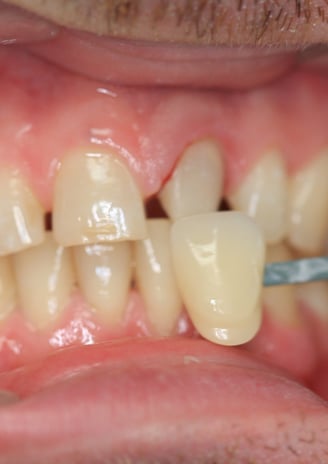

4. Prova estetica e inserimento della corona definitiva:

La nuova corona è stata prima provata per valutarne il colore, la forma e la precisione. Dopo aver ottenuto l'approvazione estetica, la corona è stata cementata utilizzando un cemento adesivo di ultima generazione, garantendo stabilità e una perfetta integrazione con i tessuti.

Dopo:

Corona completamente integrata con i denti vicini, senza differenze di colore o forma.

Stabile grazie al nuovo perno moncone in fibra di vetro.

Trattamento endodontico corretto e completato con successo.